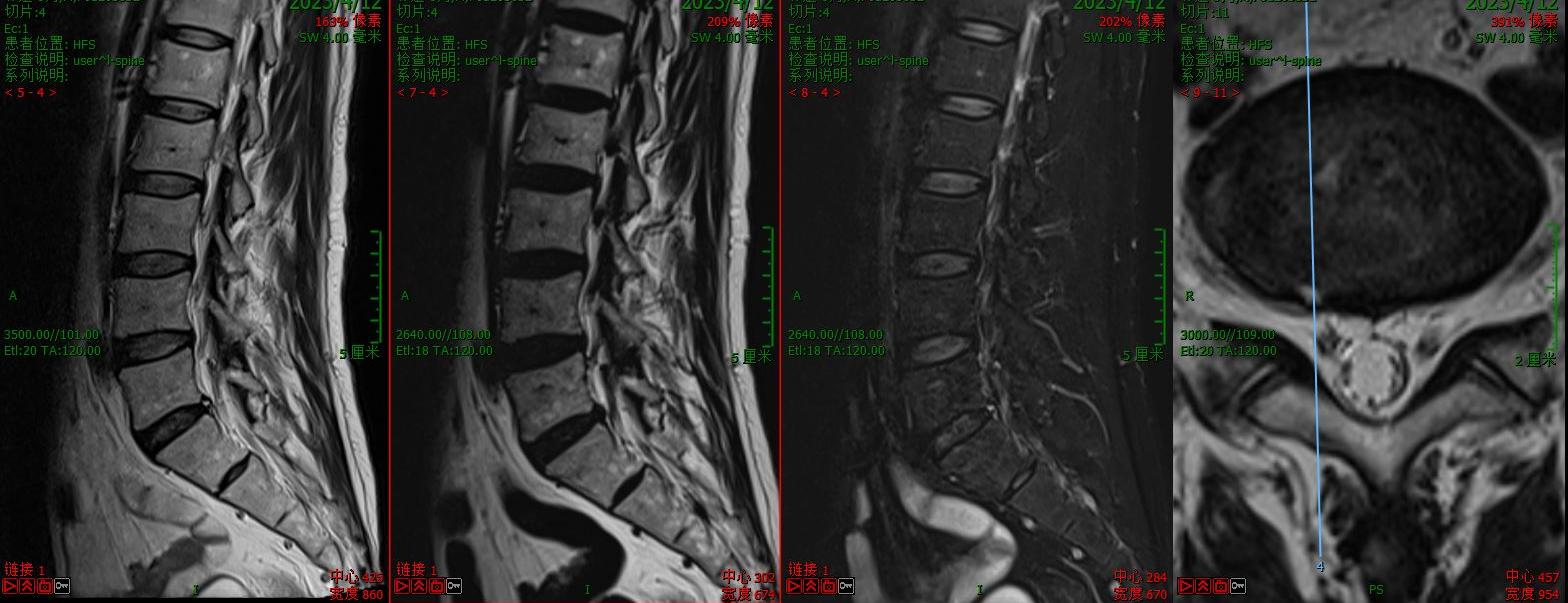

第二例病例为腰椎峡部裂患者。为其实施了VBE下的经椎间孔椎间融合术(TLIF)。患者术前腰痛伴右大腿后方疼痛1年余。术后第二天可下床活动,腰腿痛缓解。

术前核磁

术前CT